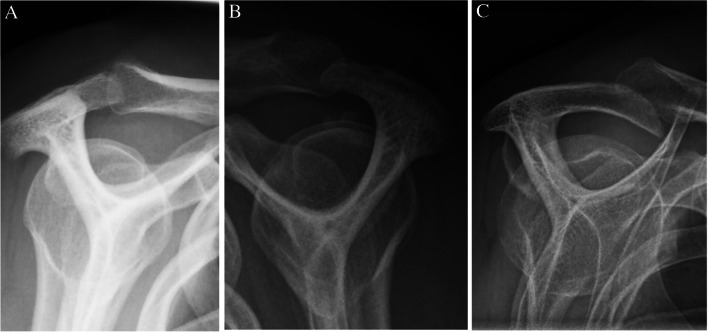

目的:研究疑似肩峰下撞击综合征(SIS)患者的特定x线表现与患者报告的肩部疼痛和残疾之间的关系。材料和方法:本横断面研究采用前瞻性研究的基线数据。研究人群包括年龄在18至63岁之间,因怀疑SIS而转诊到骨科诊所的患者。首次到骨科就诊前的影像学检查包括肩峰下钙化、肩峰形态特征(即肩峰类型和骨刺)、肩锁骨关节炎、既往肩关节脱位的迹象(Bankart/Hill-Sachs病变)和建筑测量(即肩峰倾斜、肩峰指数和肩峰外侧角)。采用牛津肩关节评分(OSS)对患者首次到公立骨科就诊时或SIS手术前的问卷回答进行肩部疼痛和残疾评估。低OSS被定义为具有评分结果:人群包括825例患者。从x线检查到完成问卷的中位时间为9天(SD = 27.1)。在校正分析中,我们发现侧骨刺,特别是鸟喙型(OR = 2.24 (95% CI 1.36-3.71)), Bankart/Hill-Sachs病变(OR = 2.49 (95% CI 1.38-4.48))和肩峰倾斜bbb35°(OR = 0.62 (95% CI 0.41-0.94))具有统计学意义。女性(OR = 2.25 (95% CI 1.59-3.18))也与低OSS相关。结论:就患者报告的肩部疼痛和残疾的相关性而言,侧刺,重点是鸟喙型,Bankart/Hill-Sachs病变和肩峰倾斜bbb35°,在临床上似乎很重要。

Materials and methods: This cross-sectional study used baseline data from a prospective study. Study population included patients age 18 to 63 years, referred to orthopaedic clinic on suspicion of SIS. Radiographic findings before first visit to a department of orthopaedic surgery comprised subacromial calcifications, acromial morphological characteristics (i.e. acromial type and spur), acromioclavicular osteoarthritis, signs of previous glenohumeral dislocation (Bankart/Hill-Sachs lesions), and architectural measures (i.e. acromial tilt, acromion index, and lateral acromial angle). Shoulder pain and disability were evaluated using the Oxford Shoulder Score (OSS) from patient's response to a questionnaire at first visit to the public department of orthopaedic surgery or before surgery for SIS. A low OSS was defined as having a score < 25. Associations between the radiographic findings and low OSS were analysed using logistic regression.